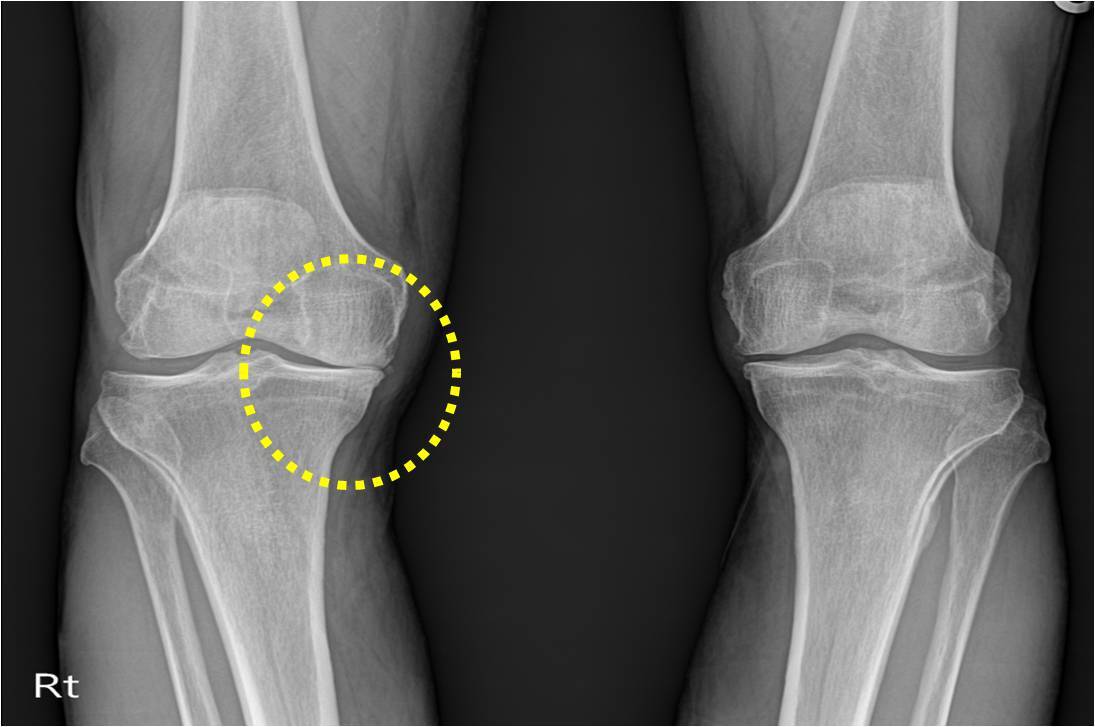

무릎 통증, 손목 발목 통증, 허리 통증 등 관절 통증은 나이가 들면서 누구나 겪을 수 있는 흔한 증상입니다. 이 중에서도 퇴행성 관절염과 류마티스 관절염은 가장 흔한 관절 질환으로, 증상이 비슷하여 혼동하기 쉽습니다. 퇴행성 관절염과 류마티스 관절염은 어떤 차이가 있을까요?

태행성 관절염과 류마티스 관절염은 모두 관절에 발생하는 질환이지만, 다음과 같은 차이점이 있습니다.

태행성 관절염과 류마티스 관절염 차이

- 퇴행성 관절염: 주로 50대 이후에 발생하며, 노인들에게 많이 발생합니다.

- 류마티스 관절염: 30-40대에서도 발생할 수 있으며, 남성보다 여성에게 더 많이 발생합니다.

- 발생 원인

- 퇴행성 관절염: 관절의 노화로 인해 연골이 마모되거나 손상되어 발생합니다.

- 류마티스 관절염: 면역체계의 이상으로 인해 관절의 활막에 염증이 생겨 발생합니다.

- 증상

- 퇴행성 관절염: 주로 무릎, 어깨, 고관절 등 큰 관절에서 발생하며, 관절의 통증과 부종, 관절의 변형 등이 나타납니다.

- 류마티스 관절염: 작은 관절인 손가락, 손목, 발가락 관절 등에서 발생하며, 관절의 통증, 부종, 열감, 피로감 등이 나타납니다.

간단히 설명하면 퇴행성 관절염은 관절을 많이 사용했을 때 통증이 생기기 때문에 활동을 시작하면 더 악화된고 반면 류마티스 관절염은 활동을 하면 통증이 줄어드는 특징이 있습니다. 두 관절염 모두 이른 아침에 관절이 뻣뻣해지는 조조강직 증상이 있지만 퇴행성 관절염은 활동을 하면 금방 좋아지지만 그냥 방치하면 둘다 만성이 되어 위험합니다.